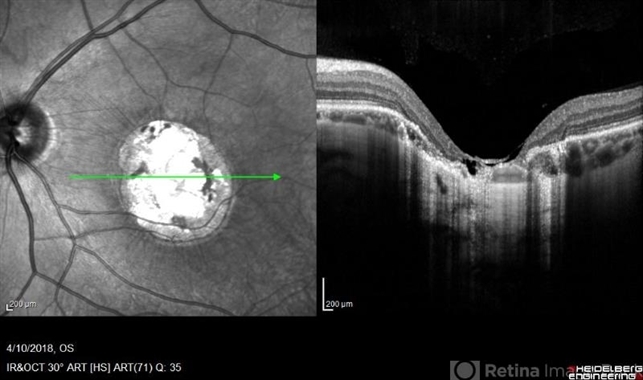

- macular dystrophy, central areolar choroidal dystrophy (CACD), retinal dystrophy, hereditary retinal dystrophy

- Left fundus OCT of a 35-year-old man with central areolar choroidal dystrophy, BCVA is 6/60